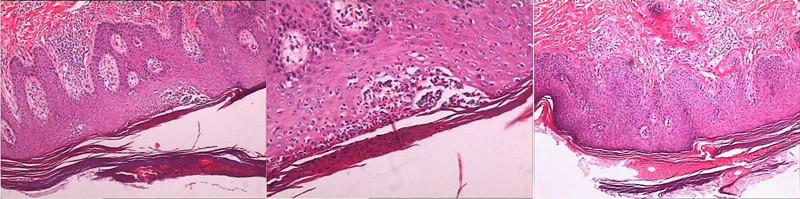

(1)组织病理学检测

银屑病的皮损组织表皮角质层有角化过度、角化不全、角质生成细胞增生、真皮乳头上延、毛细血管增生及周围有少量淋巴细胞浸润等特征性的改变,对此进行皮损的组织病理学检查有助于辅助病情的诊断,并以此为依据来判断病情的严重程度。

银屑病病理特征:角化不全,皮突延长,表皮呈银屑病样增生,乳头上延,上方粒层变薄、消失,

真皮浅层血管扩张,淋巴细胞、组织细胞及中性粒细胞浸润。